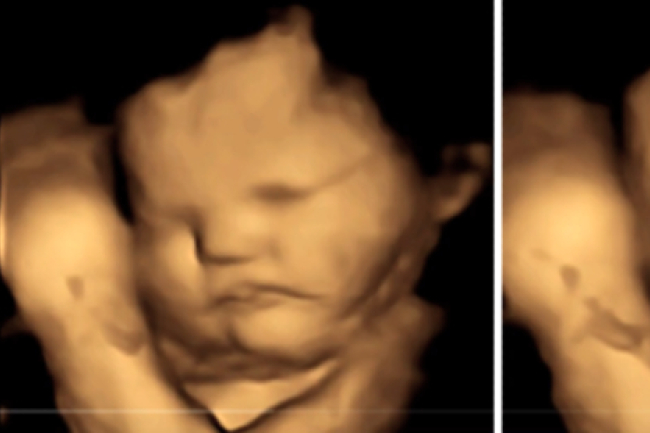

子宮嬰兒有沒有生命?3D超聲波圖片揭開秘密

子宮內的嬰兒究竟有沒有生命?一張3D超聲波圖片揭開當中秘密。